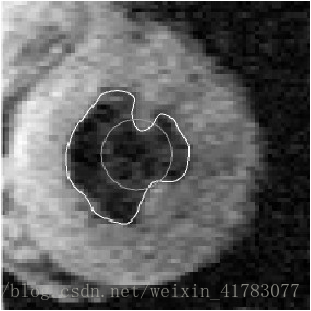

形变模型按其不同轮廓曲线的表达形式,可分为参数形变模型[6]和几何形变模型[7-8]两种。参数变形模型在变形过程中以显式参数的形式表达曲线或曲面,该表达形式允许与模型直接交互,利于模型快速实时地实现。然而,变形过程中发生拓扑结构变化时该方法难以处理。相反,几何形变线模型将活动曲线看成是两个区域的分界线,活动曲线的运动过程就是分界线的进化过程。这样,轮廓曲线运动过程就独立于轮廓曲线的参数,因此可以自动处理拓扑结构的变化。 图4(a)所示为一个心脏 MR 图像上应用形变模型(或者称为活动曲线)进行分割。图4(b)中,活动曲线在图片中初始化为一个圆,然后随后慢慢形变为左心室的边缘曲线。

(a)心脏 MR 图像 (b)左心室分割结果

图4 使用形变模型提取左心室MR 图像的内壁